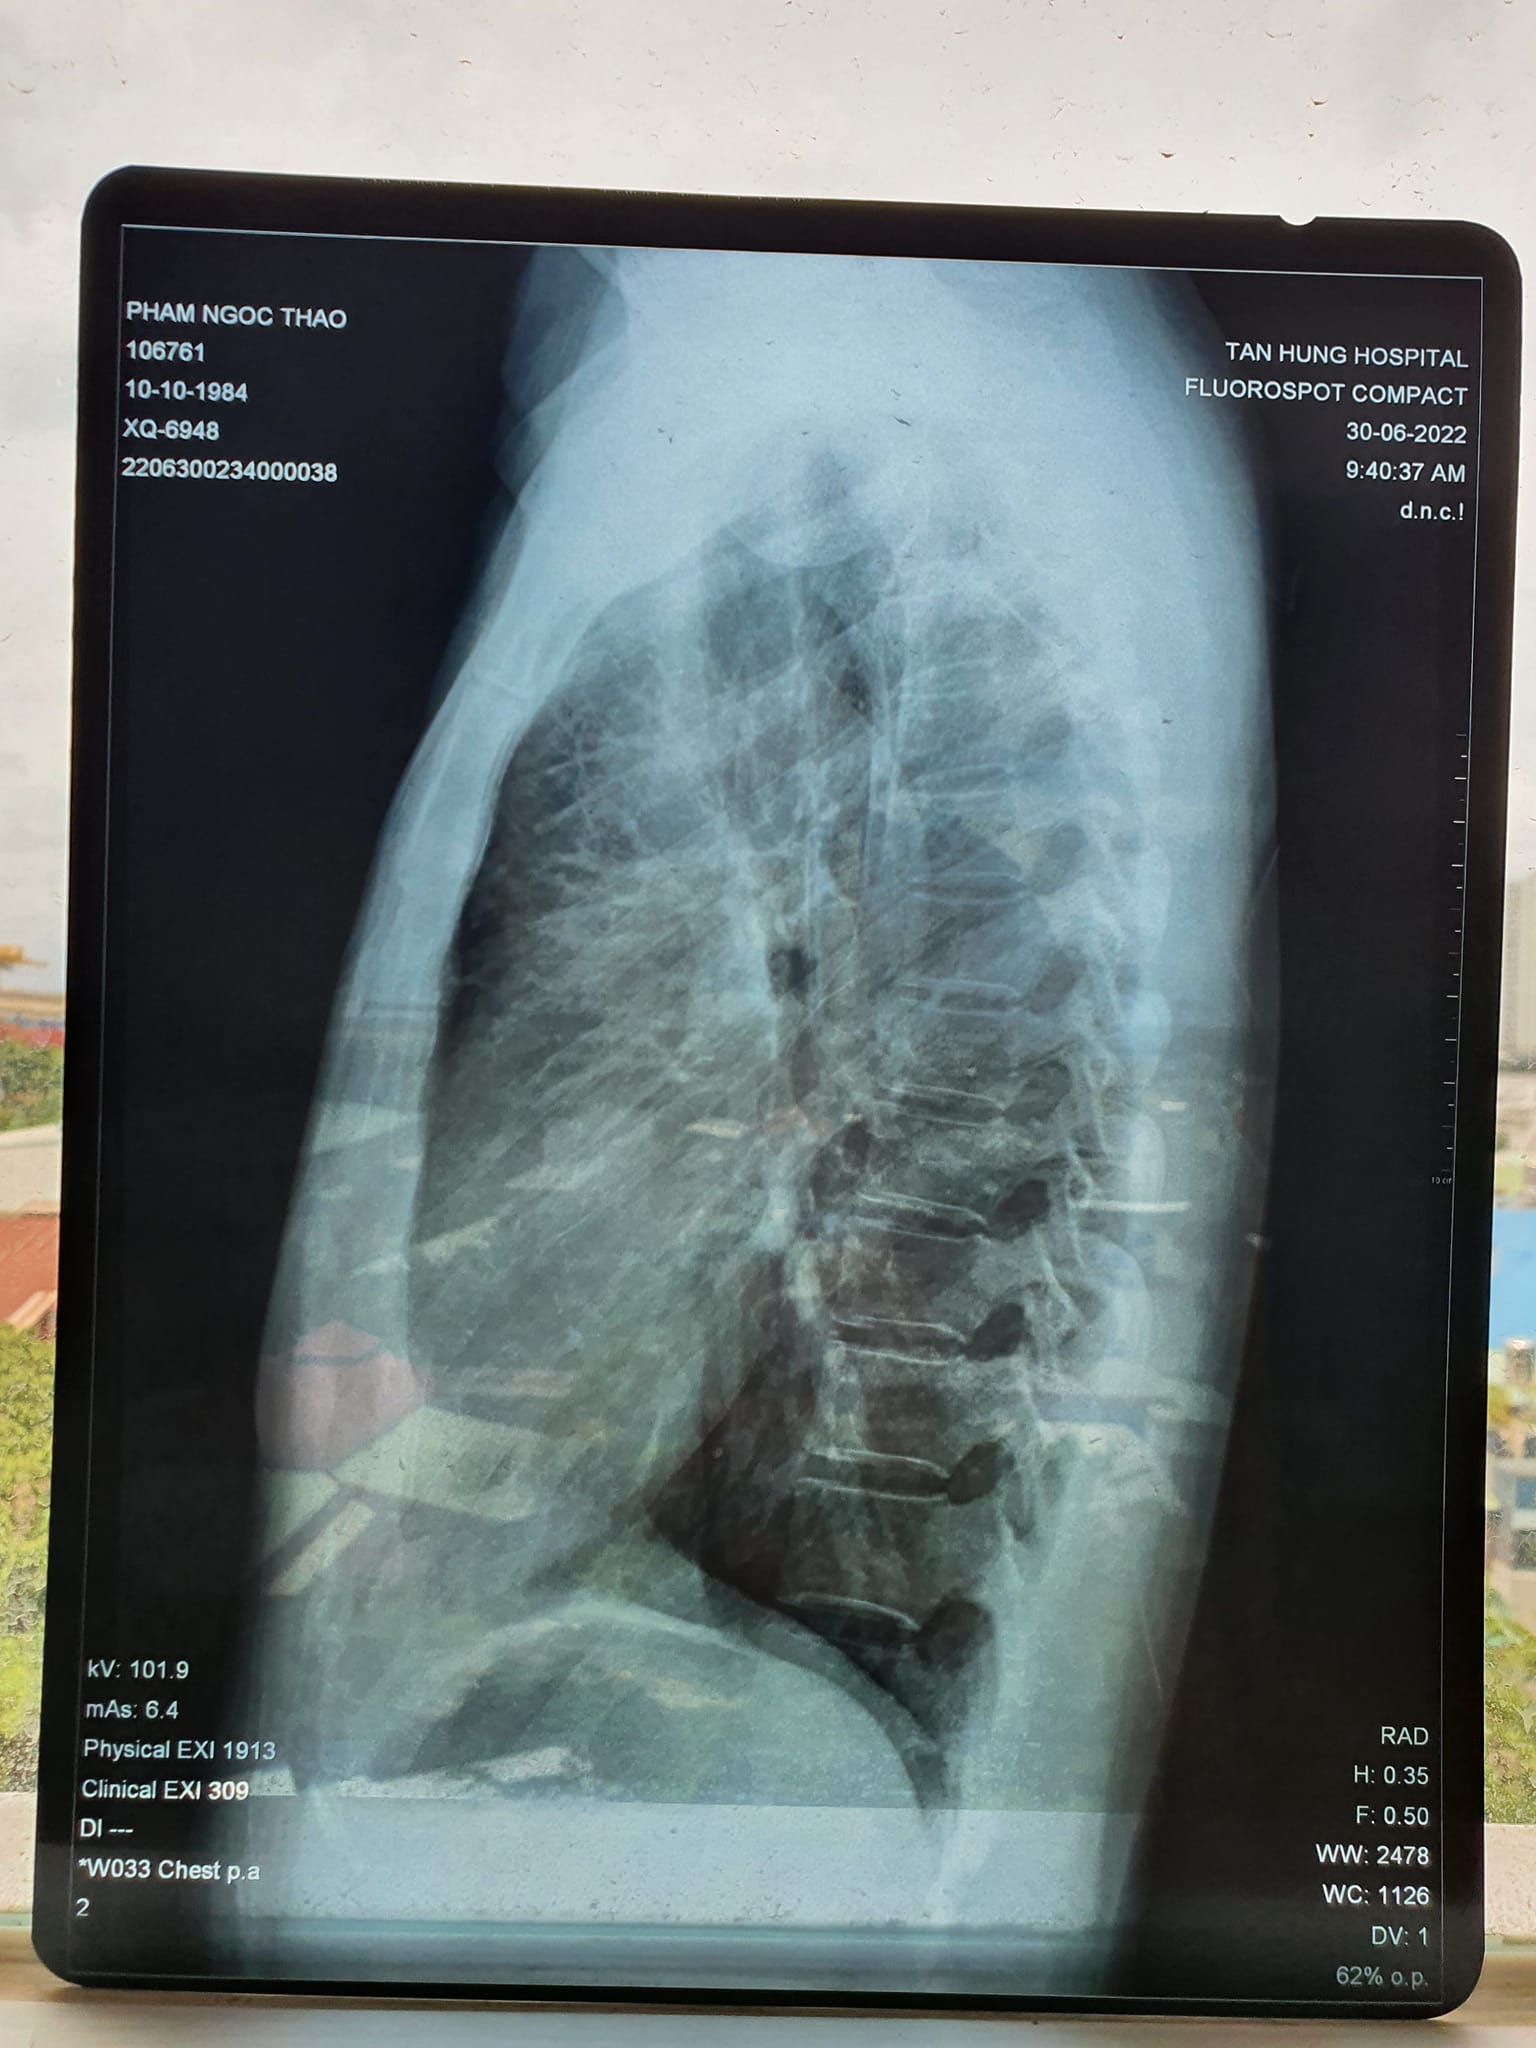

“Thầy còn nhớ ca bệnh năm ngoái chữa viêm phổi cho vợ em không? Thầy chữa 2 tuần liên tục đỡ rồi vợ em về không phải uống thuốc và sinh được bé nhà em. Giờ có biểu hiện lại vợ em đi khám thì có khối u trong phổi. Nên em không thực hiện mổ theo lời bác sĩ nữa mà em muốn nhờ thầy chữa tiếp ạ. Chữa bằng Năng lượng sinh học 2 tháng sau thì chụp X quang lại và CT lại cho kết quả. Chụp X quang thẳng không thấy tổn thương nữa, xong bác sỹ nói chụp nghiêng cho rõ hơn cũng không còn tổn thương. Rồi em yêu cầu chụp CT cho chắc thì kết quả là không thấy khối u nữa ạ. Dạ em cảm ơn thầy nhiều nhiều nhé”

Kết quả X quang và CT sau khi chăm sóc sức khỏe bằng Năng lượng sinh học vào ngày 30/6/2022